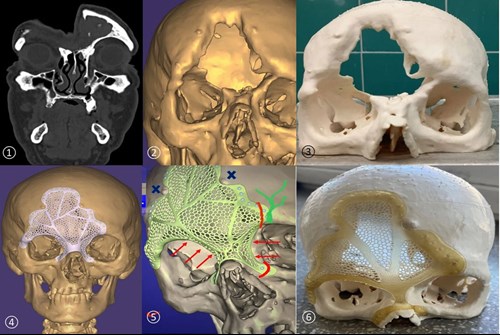

Advances in three-dimensional (3D) printing, or additive manufacturing, allow precise layer-by-layer fabrication of anatomical structures using digital imaging data. In skull bone reconstruction, a virtual 3D model of the patient’s skull can be generated from high-resolution CT scans. The missing or damaged surface is digitally reconstructed through mirror mapping, surface interpolation or slice-based reconstruction under the supervision of the surgeon and engineer [2,3]. A customised implant is designed and 3D-printed to fit the missing sections with sub-millimetre accuracy [4]. The main steps of the PSI production are outlined and listed in Table 1 and Figure 3.

Figure 3: High-resolution CT head scan (1), 3D virtual image of the head (2), 3D-printed skull from inexpensive material (3), patient-specific implant (PSI) designed and virtually matched to restore the bone defect (4), refining the PSI design (5), plastic prototype of the PSI paired with the plastic skull to simulate the surgical situation (6).